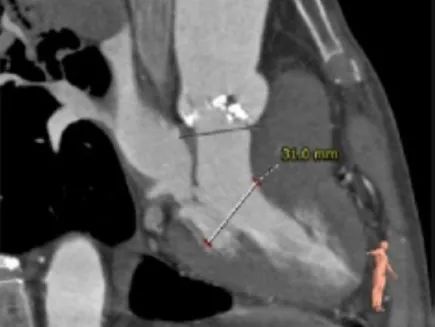

主动脉根部测量:

ANNULUS

SOV DIAMETER

LVOT

STJ

ASCENDING AORTA

LEFT VENTRICLE

冠脉高度测量:

LEFT CORONARY

左冠开口高度16.0mm

RIGHT CORONARY

右冠开口高度17.0mm